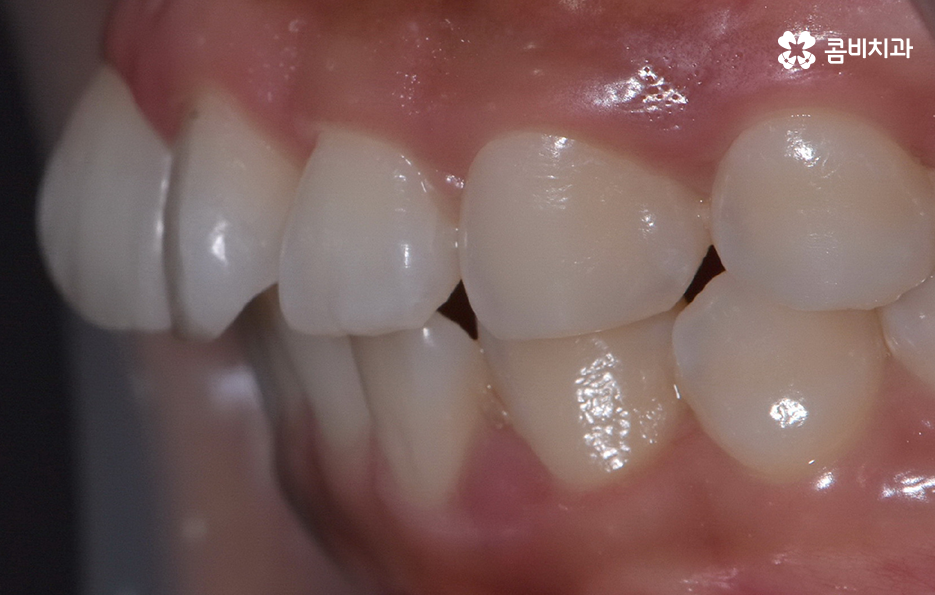

특히 앞니는 사람의 첫인상과 발음을 결정짓는 중요한 치아라 조금만 틀어져도 눈에 잘 띄고, 스스로도 불편함을 크게 느끼게 되는데 앞니 틀어짐 교정 방법의 차이는 기본적으로는 치열의 복잡성이나 치아가 이동해야 하는 정도, 교합 등의 차이에서 나타나기 때문에 치료 방법을 구체적으로 이해하기 위해서는 앞니가 틀어지는 원인과 치아교정의 원리를 알아가는 것이 도움이 될 거예요

앞니가 틀어지는 원인부터 살펴보면 대표적인 원인은 치열 공간의 부족으로 치아는 제자리에 가지런히 놓이기 위해 충분한 공간이 필요한데, 치아 크기는 정상인데 턱뼈가 작거나, 젖니가 너무 일찍 빠져 앞니가 원하는 방향으로 자리 잡지 못하면 틀어짐이 쉽게 나타날 수 있어요

특히 앞니는 치열에서 먼저 눈에 띄는 자리라 공간이 조금만 부족해도 서로 밀리며 비틀리거나, 한쪽으로 회전하는 형태로 틀어지는데 어린 시절 안좋은 습관이나 편작 습관이 있던 사람들도 턱뼈 성장 불균형이 나타나 치열 공간이 부족해지는 일이 나타날 수 있었어요

이처럼 앞니 틀어짐은 다양한 원인에 의해 나타날 수 있는데 앞니 틀어짐이 경미한 수준일 때 어떤 교정 방법이 효과적인지 살펴보면 특히 앞니 틀어짐이 심하지 않을 때는 전체 교정보다 부담이 적고 기간도 짧은 경우가 많으며 중요한 건 원인을 정확히 잡고 그에 맞는 치료를 선택하는 것이라 할 수 있었어요

앞니 틀어짐 교정 방법 경미한 수준일 때는 부분 교정 방식은 치료 기간이나 방법 면에서 비교적 간단한 치료가 가능한데 앞니 6개 정도에만 브라켓을 부착해 미세한 틀어짐을 바로잡는 방식으로 치아가 크게 회전하지 않았거나 공간이 약간 부족한 정도라면 효과적이며 기간도 보통 3~6개월로 짧은 편으로 이 방식은 앞니 배열을 빠르게 정리하면서도 자연스러운 라인을 만들 수 있어요.

두 번째 방법은 투명 교정(인비절라인 등)으로 앞니만 틀어진 경우 투명 교정은 효율적이고 눈에 띄지 않아 일상생활도 편한데 경미한 앞니 틀어짐은 투명 교정이 자연스럽고 부담이 적은 방식으로 투명 교정으로 앞니를 조금씩 배열을 맞추는데, 특히 벌어짐이나 약한 회전 교정에 효과가 좋으며 이러한 방식은 투명교정 장치의 착용 시간이 중요하기 때문에 하루 20시간 정도 착용해야 원하는 속도, 결과가 나온다는 특징이 있어요.

결론적으로 앞니가 틀어지는 이유는 생활습관, 구조적 문제, 뼈의 변화, 혀의 위치, 교합 등 다양하게 얽혀 있으며 특히 틀어짐이 경미할 때, 혹은 앞니의 변형이 시작되는 초기에는 비교적 간단한 교정 방법으로도 충분히 개선할 수 있고, 비교적 치료 기간도 짧아 부담이 적지만 중요한 것은 원인을 함께 해결해야 재발을 막을 수 있다는 점으로 무엇보다 나에게 적합한 치료 계획을 경험 많은 교정 전문의와 충분히 상의하여 판단하시길 바라고 있어요